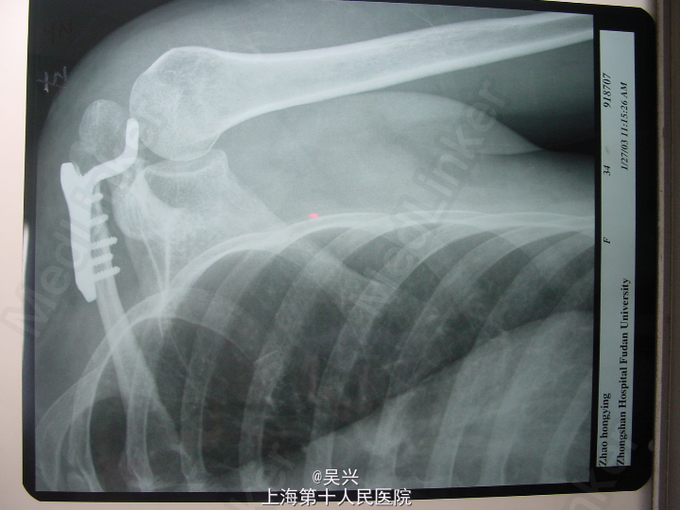

诊断:左肩锁关节三度脱位。 处理:完善术前准备后予行左肩锁关节脱位切开复位,修复喙锁韧带、肩锁韧带,锁骨钩钢板固定。

随访:术后第二天患肢三角巾悬吊保护下,左肩主动外展,前伸活动,三周后去除三角巾左肩主动功能锻炼,6周左肩功能恢复正常。 讨论:肩锁关节三度脱位是切开复位的指证,手术方式很多,其中锁骨钩钢板固定是其中一种有效的方法,但需注意锁骨钩切勿太深、太长,以免损伤肩袖,影响肩关节功能,术中应该注意修复喙锁韧带、肩锁韧带,以免发生内固定失败和脱位复发。